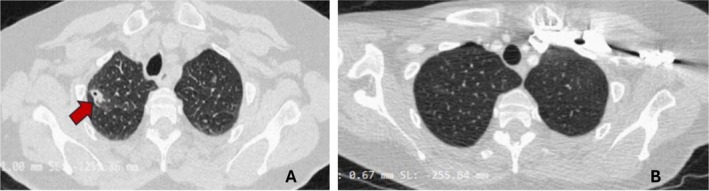

Lemierre syndrome (LS) is a rapidly progressing disease characterised by a recent oropharyngeal infection, complicated by septic emboli and thrombophlebitis of the internal jugular vein (IJV). We describe a case of a 65-year-old woman who presented to the emergency room with a 14-day history of progressive occipital headache, fever and odynophagia. Radiological investigations showed bilateral IJV thrombophlebitis, multiple cavitated pulmonary nodules suggestive of septic emboli and a subsegmental pulmonary arterial thromboembolism. A diagnosis of LS was made. The patient received antibiotic treatment with intravenous ceftriaxone and clindamycin for 2 weeks, followed by 4 weeks of oral clindamycin at home and anticoagulation with enoxaparin followed by warfarin. One-month follow-up imaging revealed complete resolution of IJV thrombosis and pulmonary findings. This case displayed the rarely reported association of pulmonary arterial thromboembolism and pulmonary septic emboli.

Abstract Image